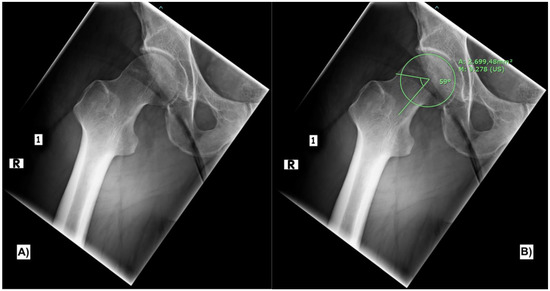

In accordance with the clinical findings, the x-ray frog leg view showed CAM deformity of the right hip and signs of osteoarthritis, as shown in Figure 1A. The measurement of the alpha angle on the same radiograph, as first described by Nötzli [6], showed a pathological value of 59° (Figure 1B).

Figure 1. X-ray frog leg view of the right hip joint showing the CAM deformity (A). Measurement of the alpha angle (B).